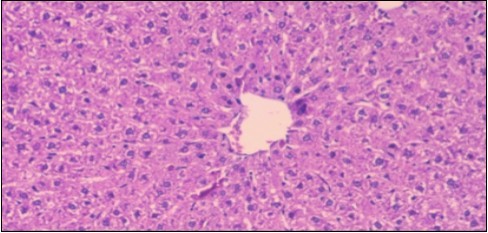

Effect of Ator, Fennel and Their Combination on the Liver of Obese Rats

The histological examination of the livers of control rats feeding standard diet showed normal architecture hepatocytes, blood sinusoid and central vein, figure 6. The rats which were fed on a (HFD), showed swollen hepatocytes with vacuolated cytoplasm filled with fatty infiltration, congested central vein and disappearance of blood sinusoids, figure 7. By comparison, the liver of rats that were treated by fennel after obesity and control mice observed nearly normal of the hepatocytes with eosinophilic cytoplasm, central vein and clear blood sinusoids and more bi-nucleated cells, figure 8. While examination of rats' liver that were treated by Ator and after the obesity appears, they showed mild fatty change in hepatocytes, few hepatocytes retain is eosinophilic cytoplasm and central vein figure 9. Liver of rats that were treated by fennel and Ator after obesity and control rats are showing nearly normal hepatocytes figure 10.

Figure 6.Photomicrogragh of liver section of control rat showing normal architecture Hepatocytes, blood sinusoid and central vein, (H&E) (40X).